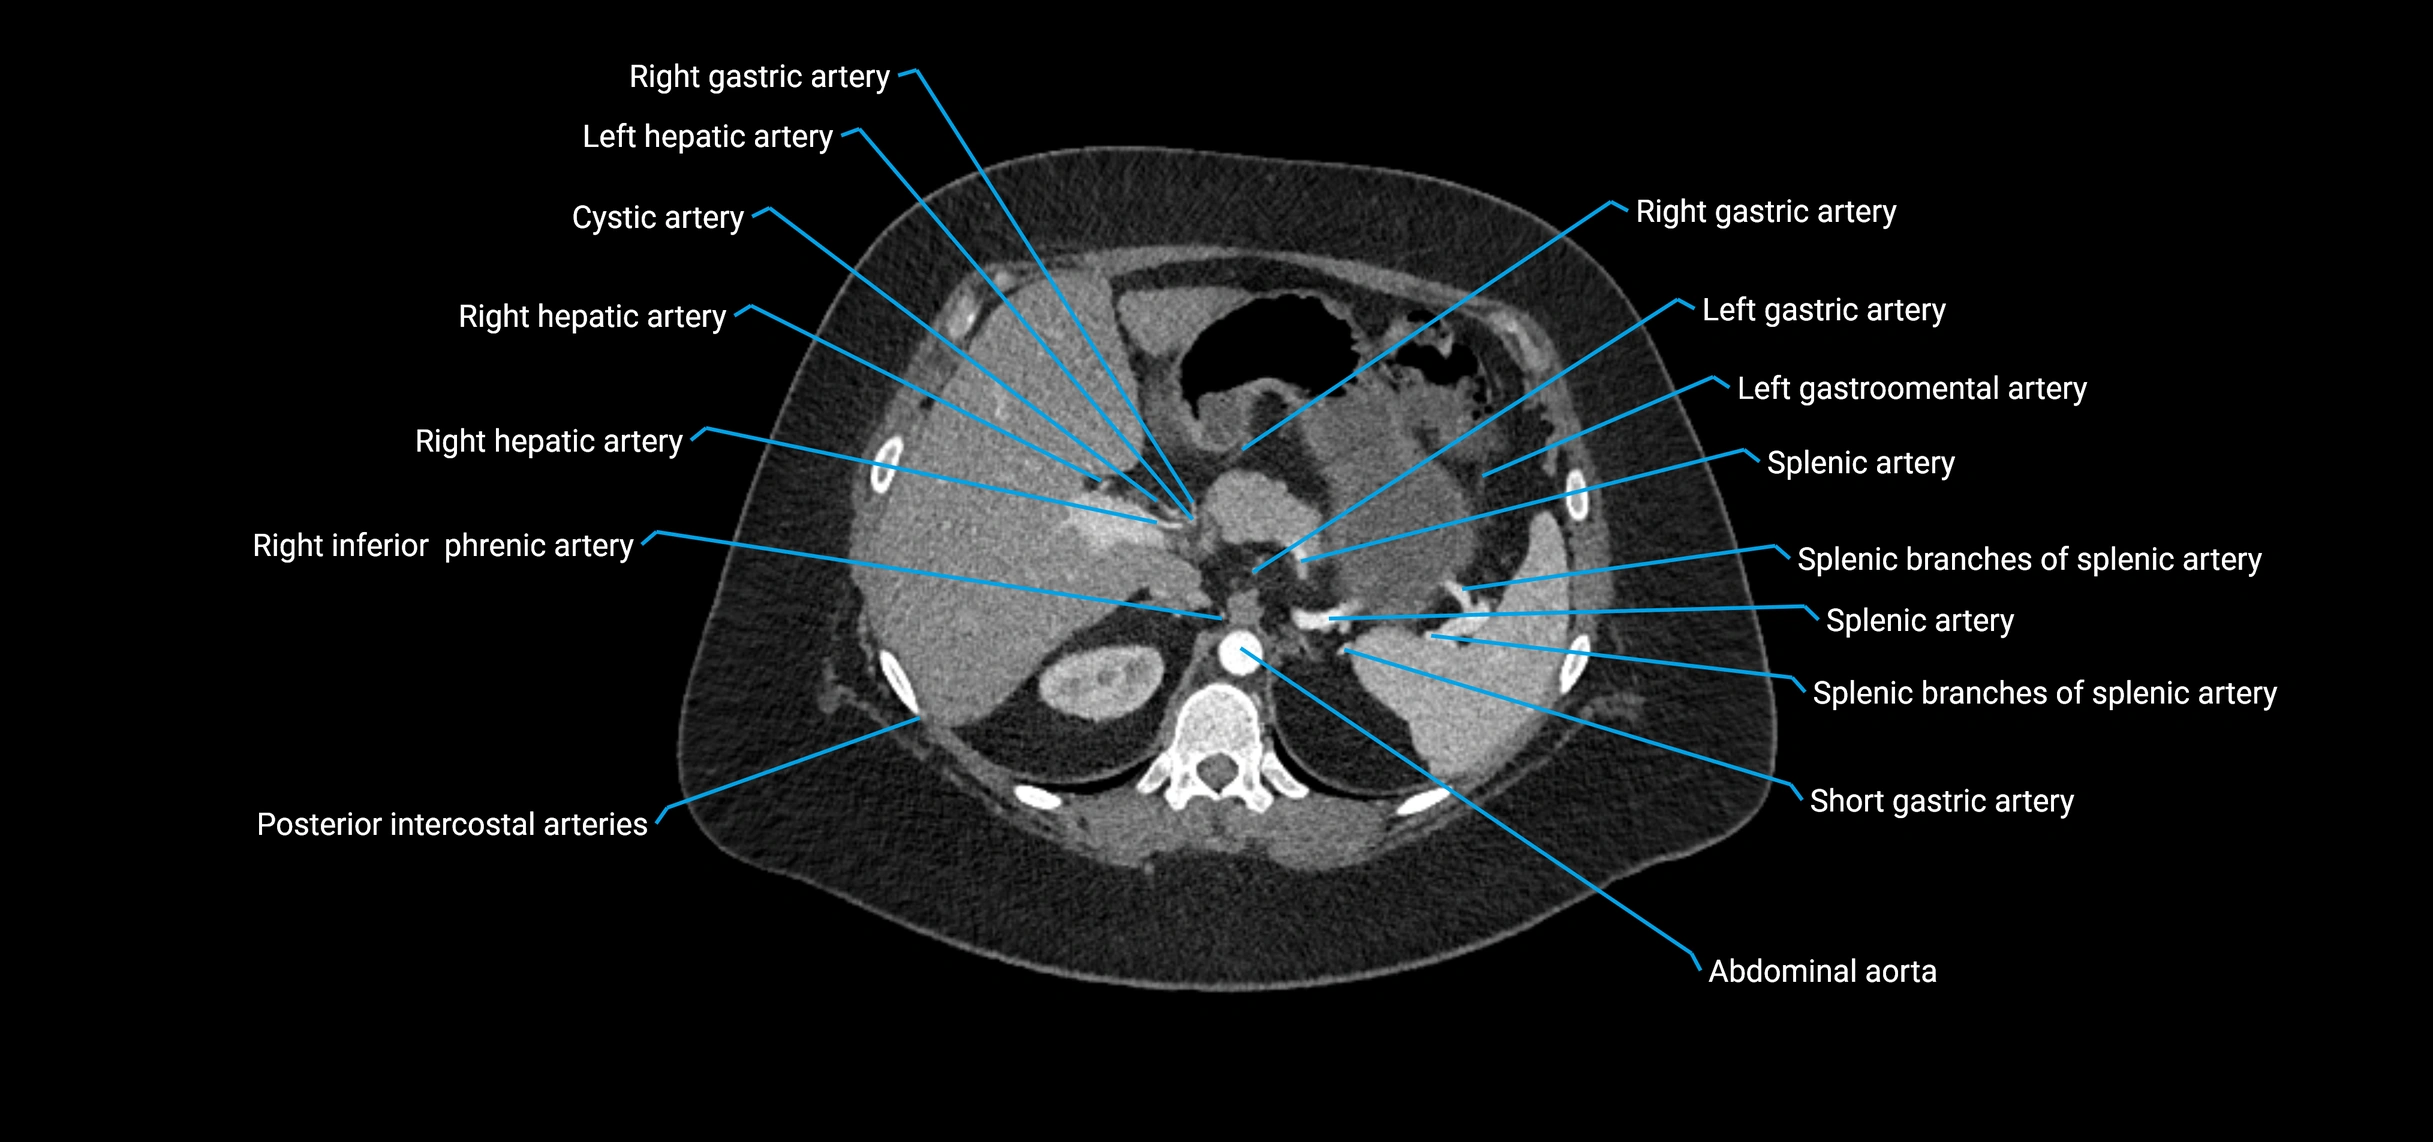

CT images

image

Contrast-enhanced CT (CTA):

• Gold standard for abdominal aortic imaging

• Provides excellent detail of lumen, wall, aneurysm, thrombus, and branch vessels

• Multiplanar and 3D reconstructions help in aneurysm measurement, stent graft planning, and dissection evaluation